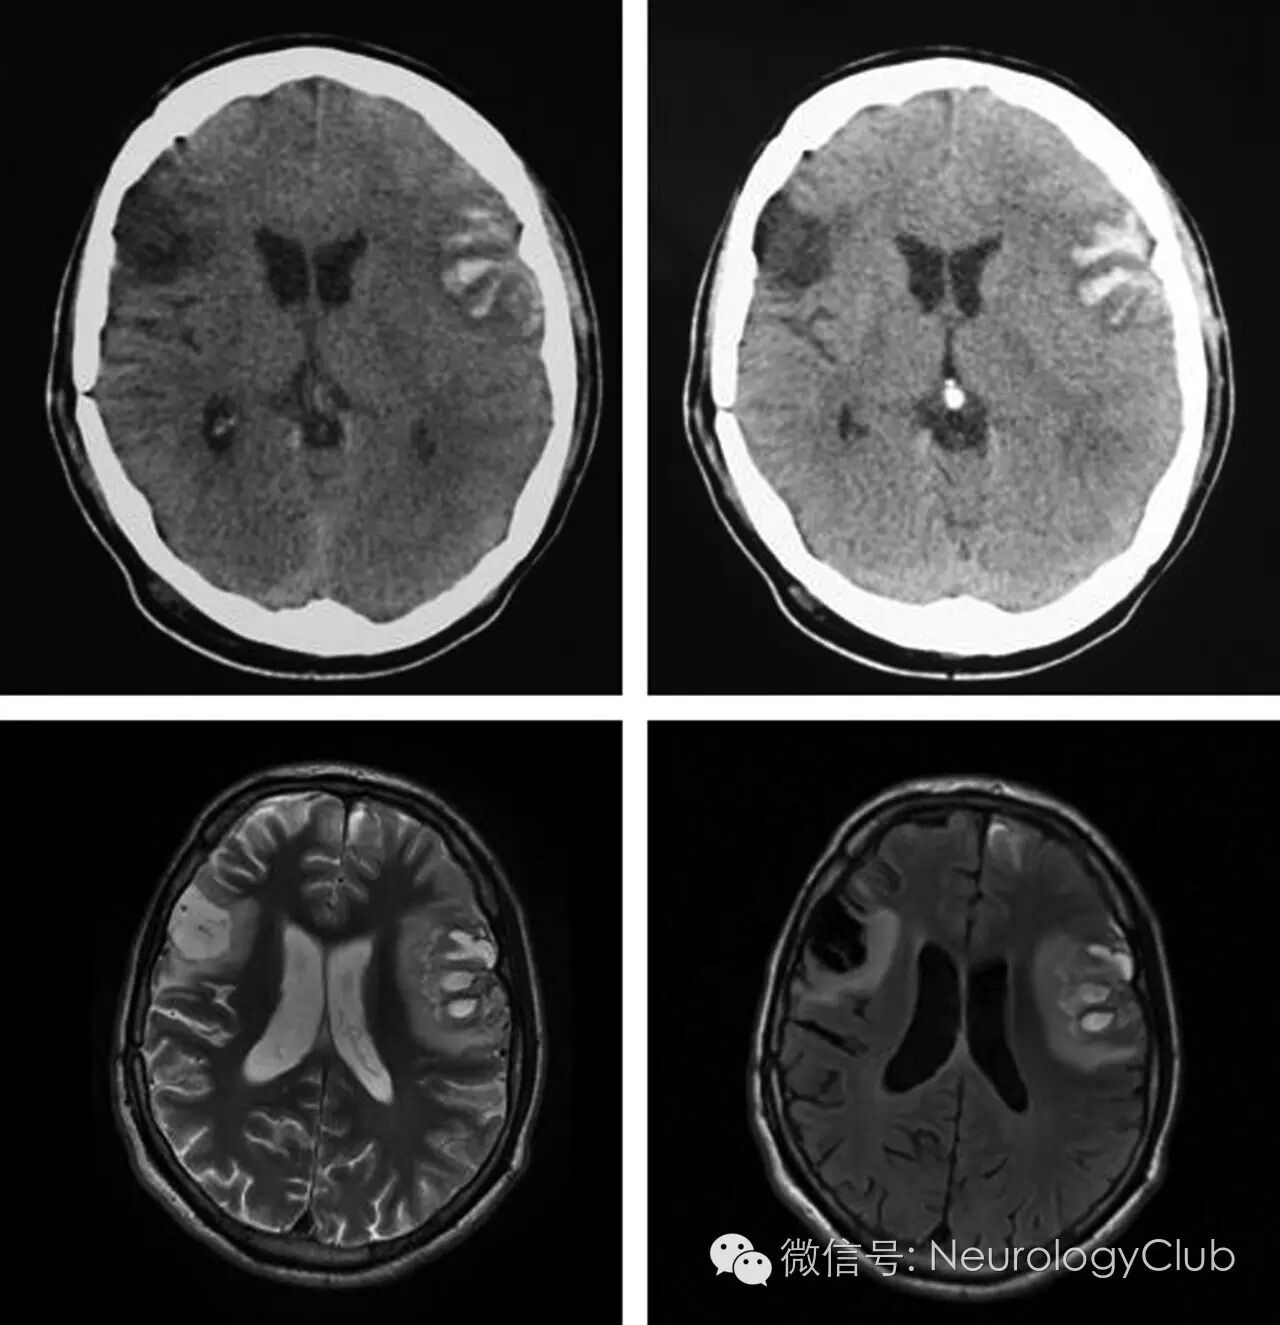

(图8:CT和MRI证实双侧创伤性岛盖病灶)